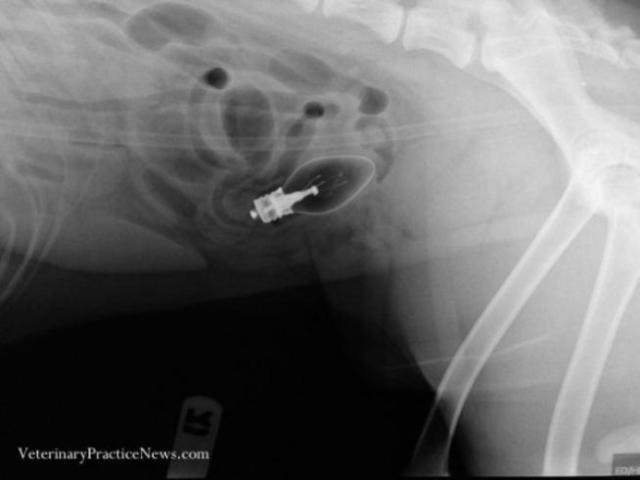

Këto janë tre kafshët e para që janë bërë pjesë e konkursit “They ate what?” (Çfarë hanë ata?”), i cili bën të mundur publikimin e fotografive më të veçanta të cilat tregojnë se çfarë kanë brenda tyre kafshët, nëpërmjet rrezeve X. Pamjet janë me të vërtetë mbresëlënëse.

Të gjitha kafshët janë në gjendje shumë të mirë dhe të gjitha objektet e çuditshme që janë gjetur në brendësi të stomakut të tyre janë hequr nëpërmjet operacioneve në klinika të ndryshme të specializuara për kafshët. Shikoni më poshtë të gjitha fotot. /a.s/noa.al